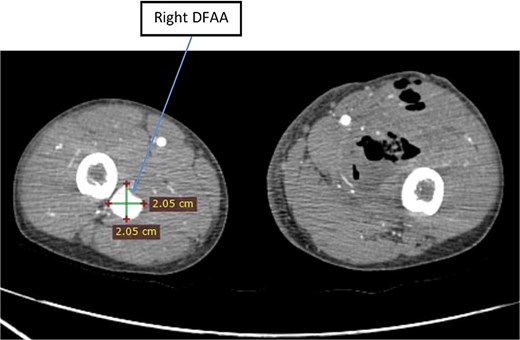

White blood cell count was 13,700 and hemoglobin was 3.4 mg/dl. CTA revealed bilateral DFAAs with the left measuring a maximal diameter of 9.32 mm with adjacent surgical pack pushing the vessels medially and a right concentric unruptured DFAA measuring 2.05 cm (Figs 1–3).

Axial image of lower limb CTA showing right unruptured DFAA with concentric aneurysmal sac.

For the incidental finding of the contralateral DFAA, the patient’s guardians were advised on revascularization but, due to difficulty to continue follow up, they opted for ligation instead. The patient underwent elective aneurysmectomy with DFA ligation for the right DFAA on the 9th postoperative day. Intraoperative finding was a 2 × 2 cm aneurysmal dilatation of the right DFA. The patient had smooth postoperative course, and he was discharged after 2 days. The patient was lost from the follow-up thereafter.